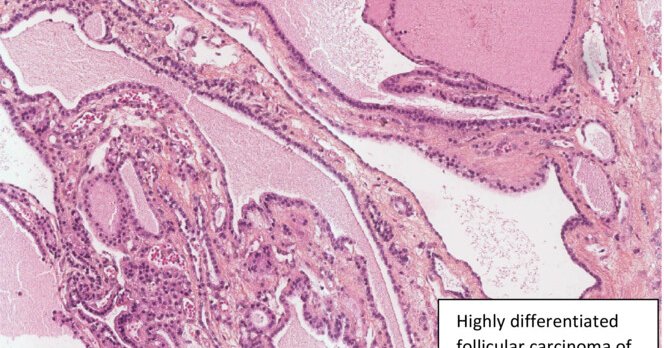

CONGRATULATIONS to winner of the Cotton prize for best paper in 2024: Role of gene sequencing in classifying struma ovarii: BRAF p.G469A mutation and TERT promoter alterations favour malignant struma ovarii - Neyrand - 2024 -#gynpath #endopath

Benign struma ovarii shows significantly fewer molecular alterations than malignant struma. BRAF and TERT promoter mutations are seen only in malignant tumours. BRAF p.G469A mutation is frequent in...